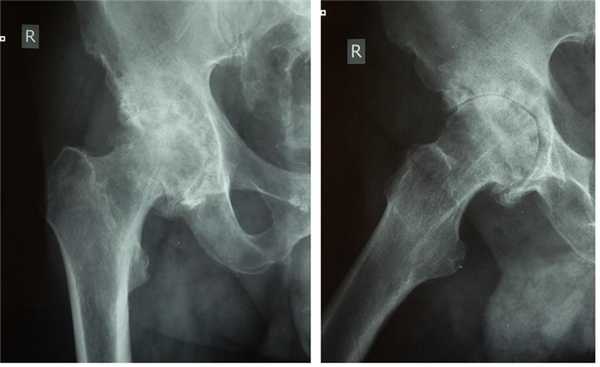

Пациент К. 68 лет, на протяжении 1 года отмечал постепенное нарастание болей и ограничение амплитуды движений в правом тазобедренном суставе. Обратился в К+31 в августе 2017 года, при выполнении рентгенографии выявлен асептический некроз головки правого бедра, коксартроз 3 стадии.

Выполнено тотальное эндопротезирование правого тазобедренного сустава эндопротезом фирмы Zimmer бесцементной фиксации, пара трения керамика\полиэтилен. Гладкое течение послеоперационного периода.

Рентгеногграммы после операции, положение компонентов эндопротеза правильное. Пациент активизирован на следующий день после операции, обучен ходьбе с дополнительной опорой на ходунки. Вторые сутки после операции, пациент ходит по палате и коридору без посторонней помощи с дополнительной опорой на ходунки.